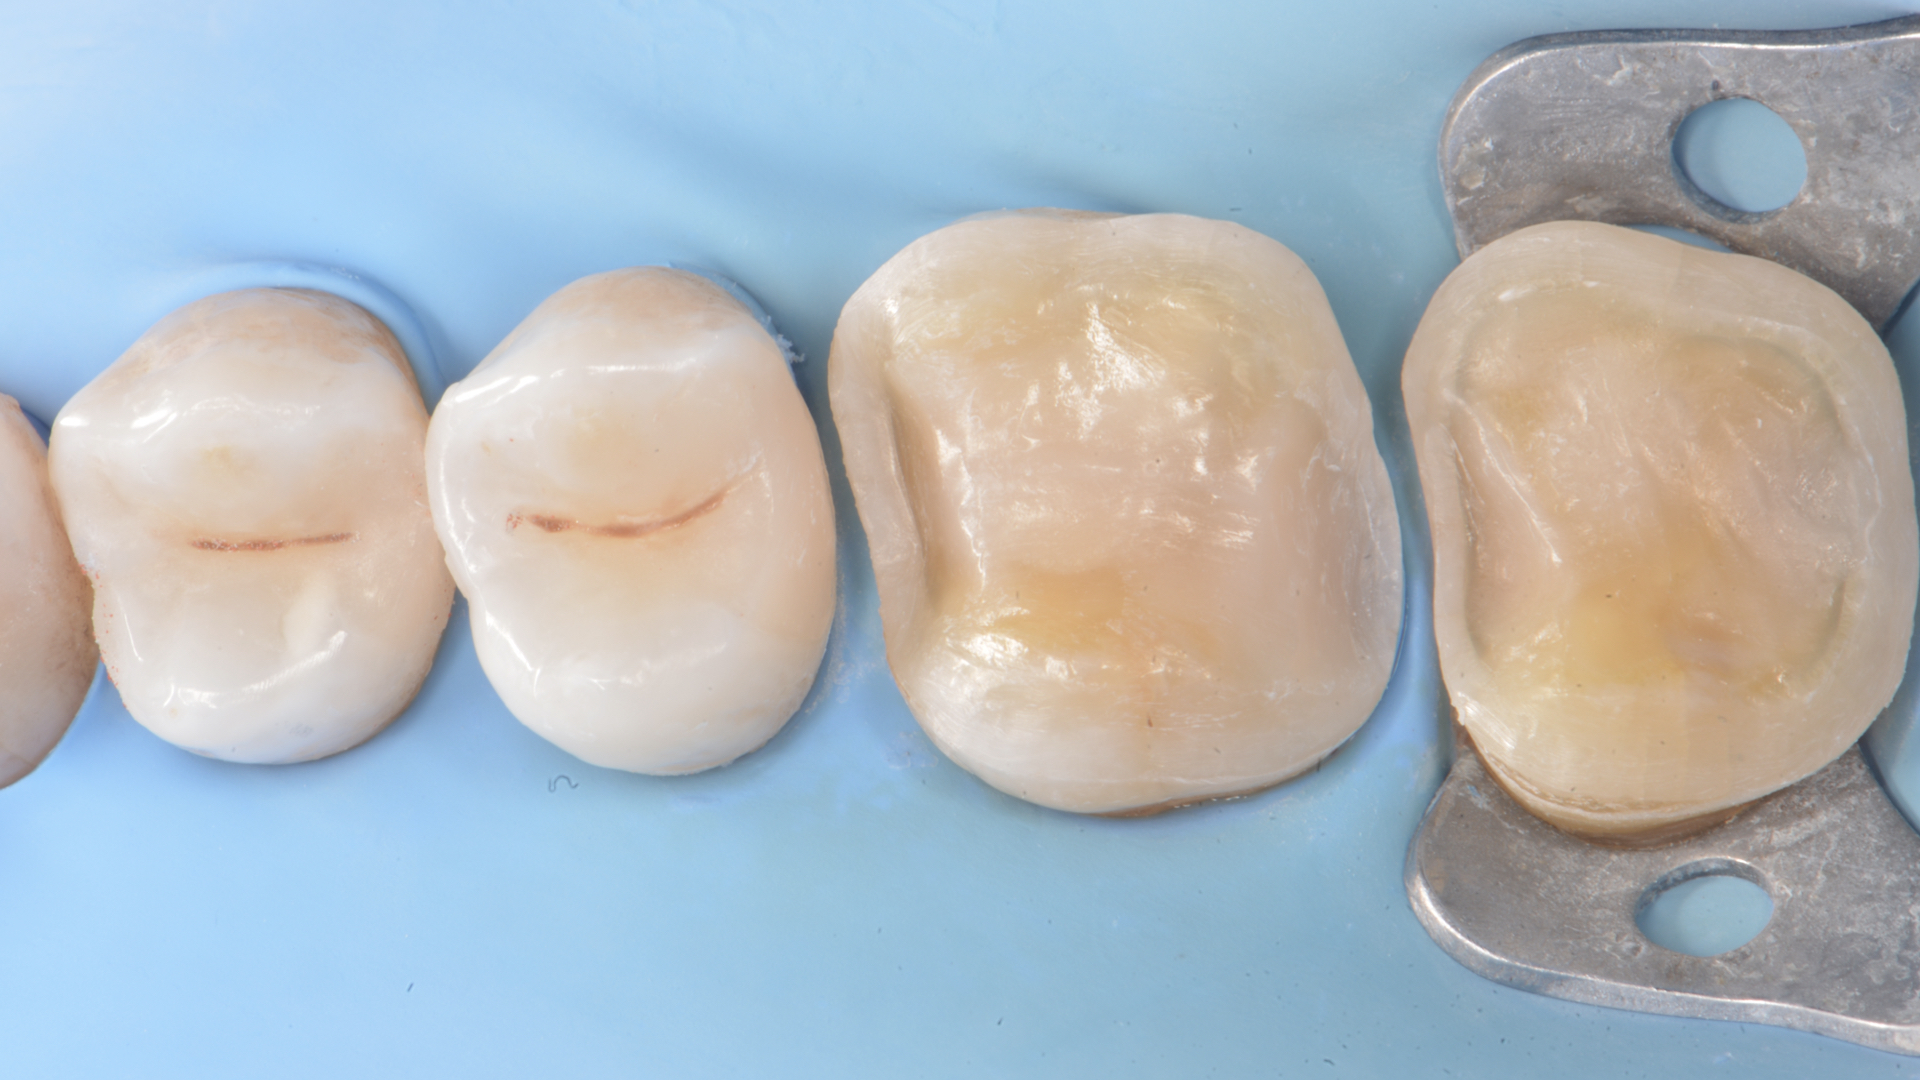

Figure 3. Teeth after caries removal Figure 4. Restoration of distal wall 1.4 (Garrison Composi-tight 3D Fusion System)

Figure 5. Restoration of distal wall 1.5 (Garrison Composi-tight 3D Fusion System)Figure 6.  Restoration 1.4-1.5 completed. Final Preparations 1.6 -1.7